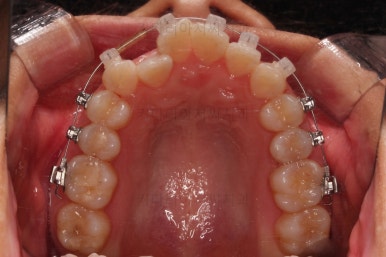

부산교정잘하는치과 초진 시 입안의 모습입ㄴ디ㅏ.

맞물림은 크게 나쁜 편은 아니었고요.

앞니 쪽이 위아래가 다 삐뚤고, 위에 작은 앞니 하나가 거꾸로 물리는 상태였습니다.

거꾸로 물리는 상황에서 특히 아래 앞니는 점점 잇몸이 꺼지는 증상이 생기면서 장기적인 치아의 수명에 영향을 주게 됩니다.